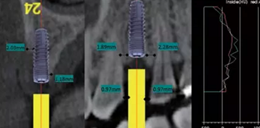

術(shù)前拍攝錐形束CT并做種植方案規(guī)劃。從圈紅處可以看出頰側(cè)骨組織不夠致密,建議備完孔后再做小翻瓣以觀察窩洞頸部的情況,圖2中的粉紅色及藍(lán)色HU值曲線顯示種植體內(nèi)部及其周圍的骨密度不高,為四類骨質(zhì),因此術(shù)中應(yīng)通過控制備孔的直徑或深度,以使種植體獲得較佳的初期穩(wěn)定性。

圖2 種植方案的規(guī)劃:a.頰舌側(cè)方向的截面圖,頰側(cè)圈紅處骨質(zhì)較疏松;b.近遠(yuǎn)中方向截面圖;c.種植體周圍的骨密度